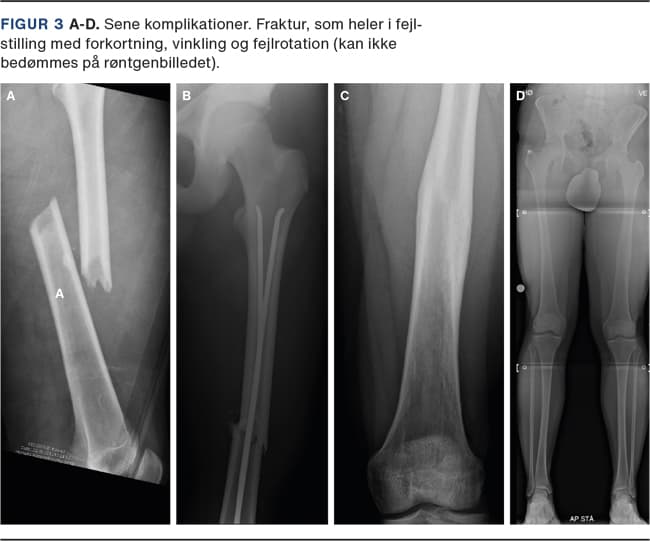

I nyere studier konkluderer man, at overvækst efter intern fiksation af både længdestabile og længdeustabile frakturer er minimal og derfor uden klinisk betydning (Tabel 1) [25, 26]. Det anbefales derfor ligesom i frakturbehandling af voksne at genskabe den anatomiske længde samt mekaniske akser og rotation (Figur 3). Komplikationer (Figur 2 og Figur 3) kan være: 1) akutte: hudproblemer og frakturskred, 2) sene: opheling i fejlstilling, som ikke korrigeres med længdevæksten, vækstforstyrrelser med påvirkning af vækstzonen proksimalt eller distalt i femur og vinkelfejlstillinger, fejlrotation og benlængdeforskel, og 3) sjældne: dyb betændelse, kontrakturer, nonunion, kompartmentsyndrom samt kar- og nerveskader.